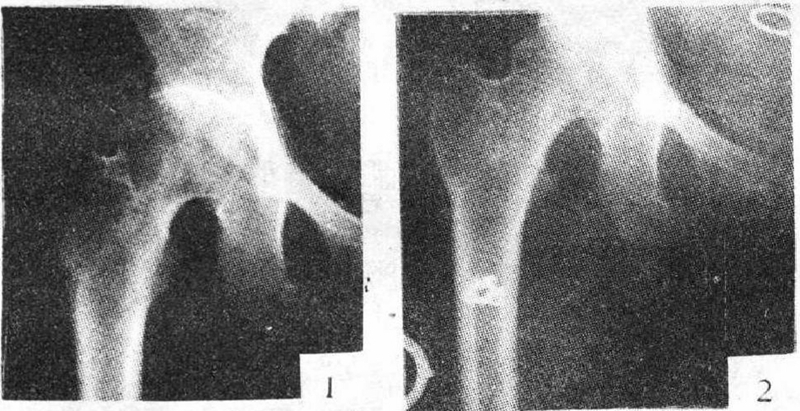

1、传统单孔(Single CD,SCD)髓芯减压术

单孔髓芯减压术是使用8~10mm的环钻或空心针,在X线透视下从转子下方骨皮质经股骨颈达到股骨头坏死区域,进而清除坏死骨组织,其临床疗效常取决于分期。

一项1992年前后手术病人的临床和影像结果,1992年以前手术的有近41%的关节需要进一步手术治疗(平均随访65个月),1992年以后手术的只有30%的关节需要进一步手术(平均随访63个)。

一项长达10年的随访,髓芯减压术股骨头坏死FicatIⅠ、Ⅱ、Ⅲ的股骨头存活率分别是96%、74%和35%。说明不同分期,疗效也有明显的区别。

一项对股骨头坏死塌陷髓芯减压手术干预后12年随访,仅有29%的患者有较满意的效果,按疾病分期,41%的SteinbergⅢ期需要THA,92%Ⅳ期需要THA。

一项对股骨头坏死髓芯减压术随访5年的存活率研究发现,FicatⅠ期疾病患者的5年生存率明显高于ⅡA和ⅡB期疾病患者,分别为75%、30%和17%。Ⅰ期疾病患者的生存率很高,但Ⅱ期疾病患者可能需要其他治疗。